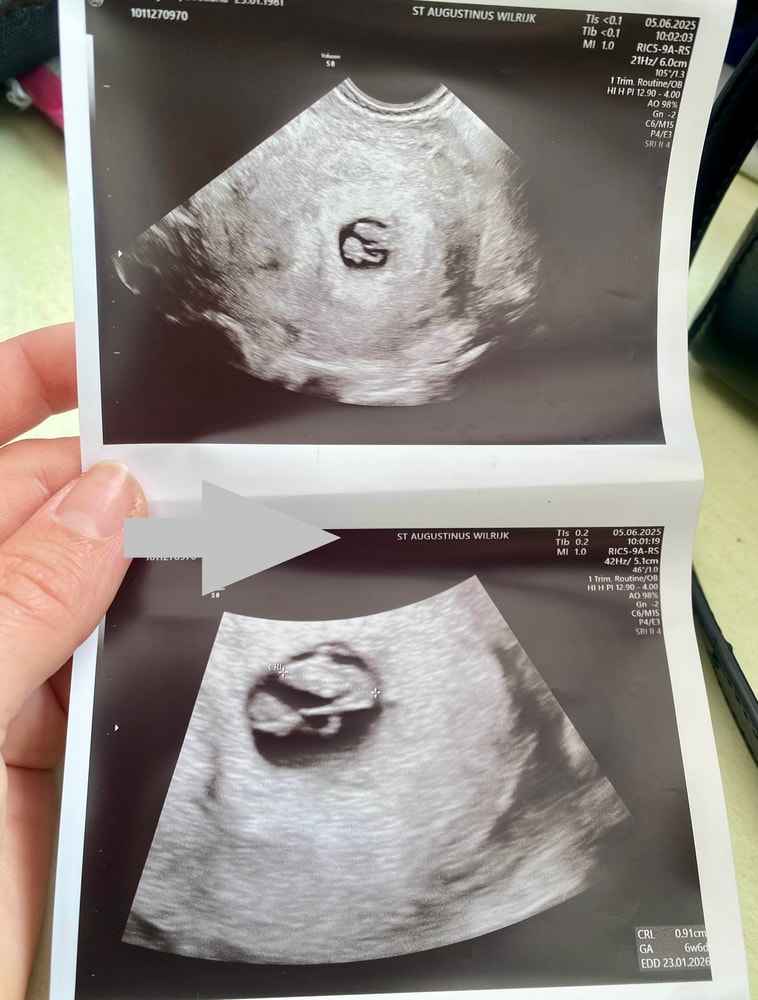

Результаты УЗИГосподи, девочки, сколько я страха сегодня пережила , ночь нормально не спала, сегодня у нас день Арафа, встала с детьми на утренний намаз, потом еле уснула, Господа Бога просила «если во блага этот малыш, пусть он будет». К врачу встреча была в 10:10 утра , выехала с дома в 8:50( ехать 60км в другой город) вышла спец по раньше зная что пробки могут быть! Всю дорогу молилась, слушала Коран(вместо музыки, вместо таро😆🤦🏻♀️) пришла в больницу, поднимаюсь( по дороге в кабинет все просила Всевышнего помочь, успокоить меня) , 🚶♀️➡️,прохожу кабинет и сидит моя РЕ ☺️говорит- ну заходи 🤭, хотя еще минут 20 надо было ждать,но видя народу нет, решила меня принять.Господи, трясло не по детски, ввела себя как будто мне лет 17 … спросила -нет ли проблем, как состояния ну и давай «дуй на кресло»🤪 …легла, только засунула эту хрень,вижу плодное яйцо и силуэт….О Всевышний, секунды счастья, потом резко спрашиваю-а сердечко ♥️ есть? Смотрит,говорит- есть , видишь бьется ….но послушать прям со звуком не дала , показатели показали что все хорошо- Итог - малыш развивается в срок, 6недель и 6 дней, предполагаемая дата -Шок - МОЙ ДЕНЬ РОЖДЕНИЯ 😂🤭23/01/2026 года !!!

Малыш -9 мм, чистота ♥️135 , сказала - все ,иди теперь к своей Гини вставай на учет, переживать якобы не чего, все идет как надо!🙏🙏🙏🙏 ах , да, есть маленькая гематома ,сказала продолжать утрик 3*200 до 12 недель а потом уже твоя врач скажет как и что! Кровь, туда сюда ни чего не сдавала,теперь заниматься дальше будет уже мой врач , записалась на следующую неделю 12/06 глянем еще раз 🙏🙏🙏Господи, защити , убереги от сглаза от всех бед всех нас мамочек ♥️♥️♥️♥️♥️♥️Девочки, боюсь даже что либо мечтать, думать, планировать, пока я в режим «ожидании всех анализов и критического срока» Пусть каждая будущая мамочка, просто кто уже мамочка - держитесь девочки, не опускайте руки, это очень важно🙏💐 мой путь 2 года, 11ый перенос ,12го по счету эмбриончика ,молю Всевышнего что бы он остался и был с мамкой на все уже почти 7 месяцев !!!! моя маленькая акулочка♥️🦈♥️